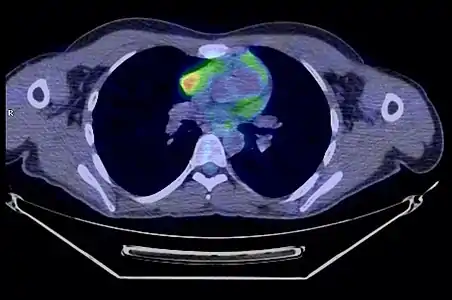

La place du TEP scanner dans le diagnostic des thymomes est encore débattue[31]. S'il existe bien une hyperfixation de la tumeur, son rôle dans le diagnostic de l'extension locorégionale reste à préciser[33].

- Thymome de type B1 en TEP scanner

Coupe transversale. Les trois clichés sont extraits du même examen.